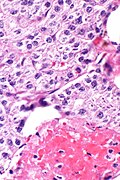

• Histologically normal parathyroid cells.

• Cytologic features not reliable for diagnosis.

• Fibrous capsule.

• Invasion of surrounding tissue - key feature.

• +/-Metastasis - diagnostic feature.

• Diagnosis of parathyroid carcinoma is like that of malignant pheochromocytoma - cytology useless, tissue invasion and metastases are the key features.